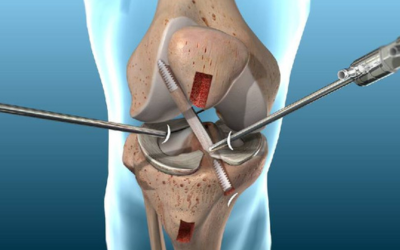

ACL surgery is a surgical procedure aimed at reconstructing or repairing the torn ligament in the center of your knee. The ACL is essential for stabilizing your knee during motion, especially side-to-side or pivoting movements.

In most cases, a graft (taken from your own body or a donor) is used to replace the damaged ligament. The surgery helps restore full knee function, allowing you to walk, run, and return to your active lifestyle.

He uses advanced arthroscopic methods for ACL reconstruction, ensuring minimal damage to surrounding tissues. This approach not only reduces the hospital stay but also speeds up the recovery process.

As the best ACL surgery doctor in Gorakhpur, Dr. Khetan uses modern arthroscopic techniques that are minimally invasive, resulting in less pain, smaller incisions, and quicker recovery times. His deep understanding of knee biomechanics makes him the top choice among patients seeking ACL surgeons in Gorakhpur.